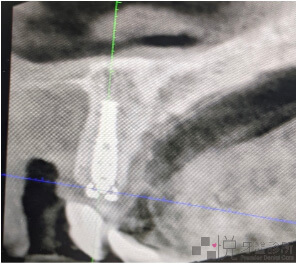

有了導航科技的輔助,在植牙的過程中不用單靠腦海內的模擬,而是用X-Guide的電腦去作精密的運算進而去即時定位,避開神經地雷區,已達到精準數位植牙的水準。

如果採用導引板植牙,傳統導引板或是數位設計出來的 3D 導引板,在前牙即拔即種的案例,最難克服的就是導引板容易位移上翹。經驗不足的話容易左右位置很準,但是植牙的牙度向前偏斜(暴牙),偏斜角度太大還有可能要重新取出植體,或是假牙的製作受限無法滿足美觀需求。

X-Guide 植牙導航機則可以即時在畫面中看到手術時的深度、位置、角度,而且可以即時校正,不斷確認裝置位置是否有移位,是最適合用在前牙立即植牙的最佳輔助工具。